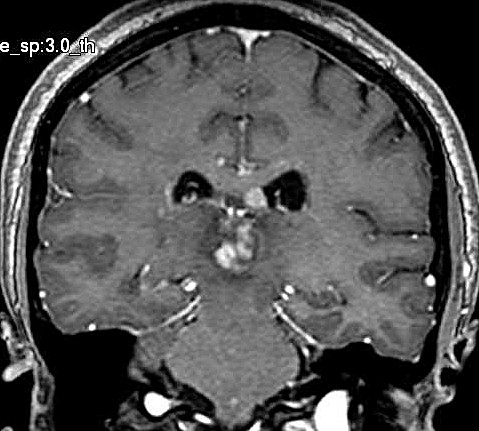

| Fem. 17a. |

| Nódulo sólido homogêneo preenchendo o III ventrículo, com limites precisos, com hipossinal em T1 e hipersinal em T2 e FLAIR, que se impregna por contraste paramagnético. Lesão menor implantada no assoalho do IV ventrículo provavelmente representa disseminação por via liquórica. |

| CORONAL, T2 | T1 COM CONTRASTE | |

| F. 17a. Tumor teratóide rabdóide atípico de III ventrículo. RM | HE | VIM, GFAP | HHF35, desmina, 1A4 | AE1AE3, EMA |